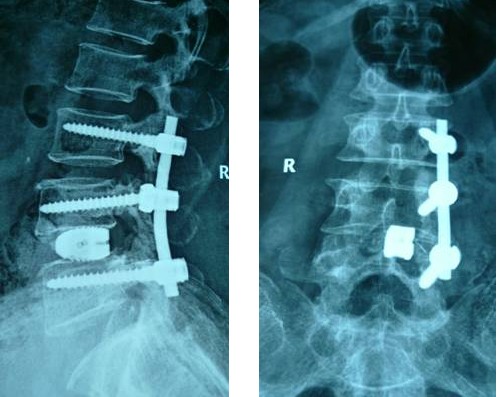

病例匯報1老年女性患者,因“反復(fù)腰腿痛10年、加重伴左下肢麻痛2月”之主訴入院,術(shù)前左下肢肌力3+級,淺感覺減退。術(shù)后腰腿疼緩解,肌力及感覺恢復(fù)正常。(1、圖2)

術(shù)后腰椎X線提示單側(cè)釘棒系統(tǒng)固定穩(wěn)妥,椎間隙高度恢復(fù)正常,融合良好。(圖2